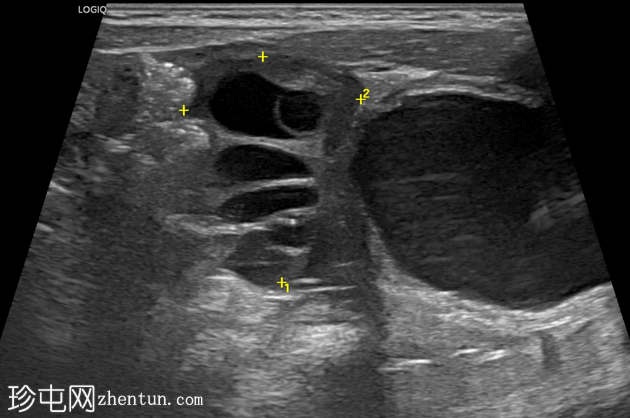

纵切面

右侧努克氏疝管长约6毫米,内含部分子宫和卵巢(大小约1.5 x 1厘米)。在整个检查过程中,这些组织均保持原位。

对侧附件呈多囊性改变,大小约3 x 1.8厘米。

上述超声特征清晰地显示了努克氏疝管的内容物及其延伸范围;其中包含患者的一侧卵巢和部分子宫组织。

这些特征符合卵巢努克氏疝的诊断。